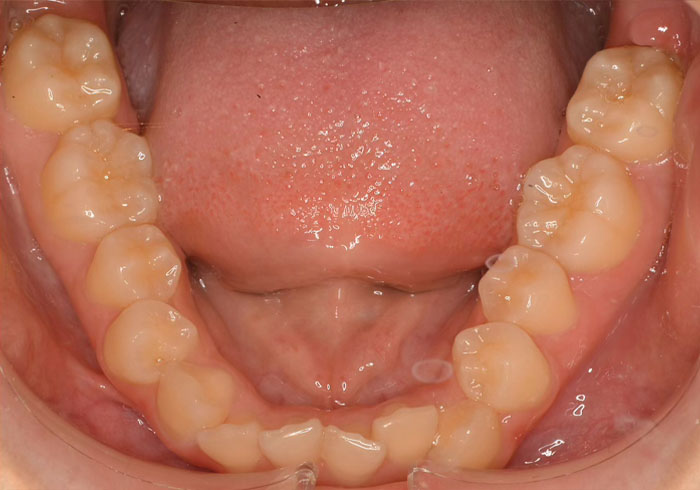

口腔内写真

治療前

治療後